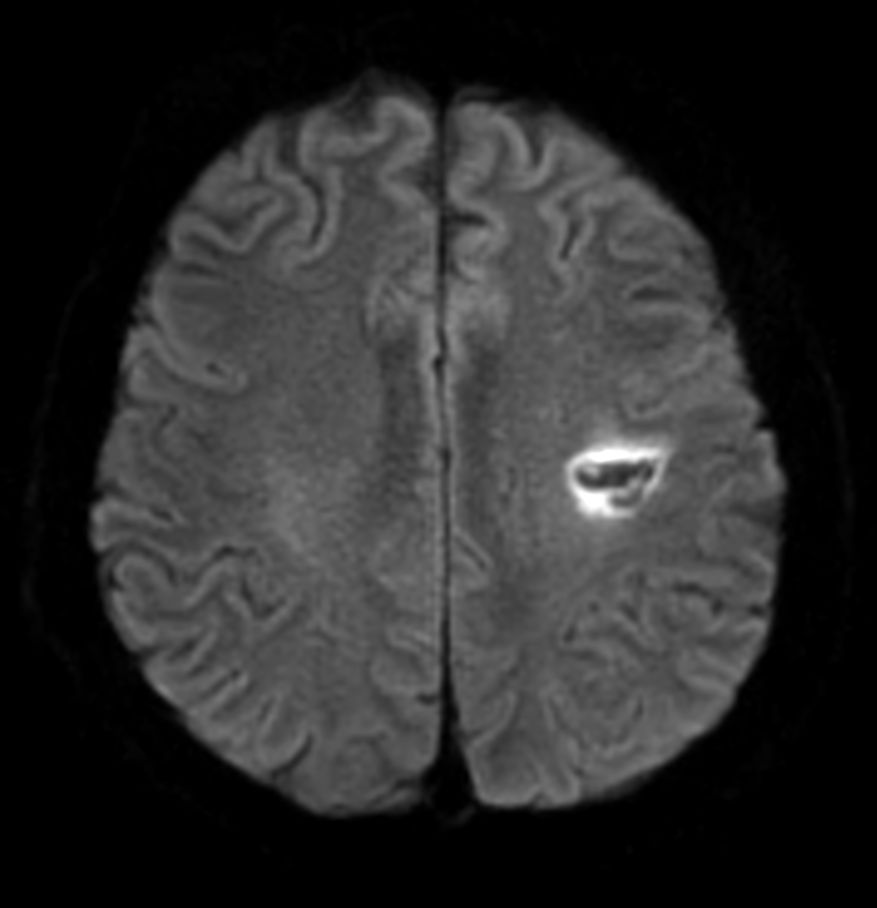

Patient with a small brain infarction. Compressed SENSE acceleration is used to speed up sequences while maintaining equal image quality. Three different diffusion methods are included; A fast 52 secs DWI EPI sequence, a high resolution DWI EPI sequence and a TSE based DWI sequence. A SWIp sequence is included offering high resolution 3D susceptibility weighted imaging to enhance contrast for deoxygenated (venous) blood or calcium deposits. 3D APT sequence is included providing contrast-free brain imaging, addressing the need for more confident diagnosis in brain neuro oncology by using the presence of endogenous cellular proteins to produce an MR signal. And a large FOV TOF MR Angiography sequence is included to check on brain vascular anatomy.

Axial DWI EPI (b1000)

Axial DWI EPI (b1000) - High resolution

Axial DWI TSE XD (b1000)